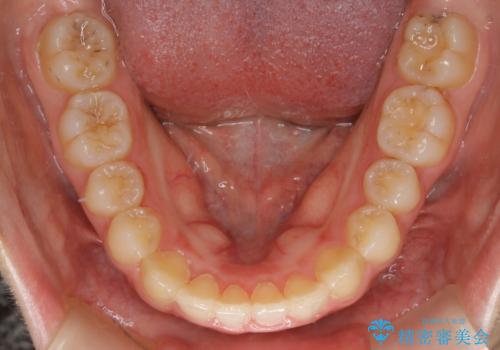

【非抜歯】すきっ歯と噛み合わせの治療

- 上の前歯のすきっ歯と下の前歯のガタつきを主訴にご来院されました。

噛み合わせの改善も同時に進めつつ、主訴の部分も効率的に治していくためマウスピース装置でゴムかけを行いながら治療を進めていきました。

正中離開(すきっ歯)

真ん中の歯が左右に開いてしまい隙間ができてしまう状態を「正中離開」といい、俗にすきっ歯と呼ばれています。

隙間を埋めていく方向に歯を移動させることで改善していくケースが多く、比較的治りやすい不正咬合のひとつとされています。